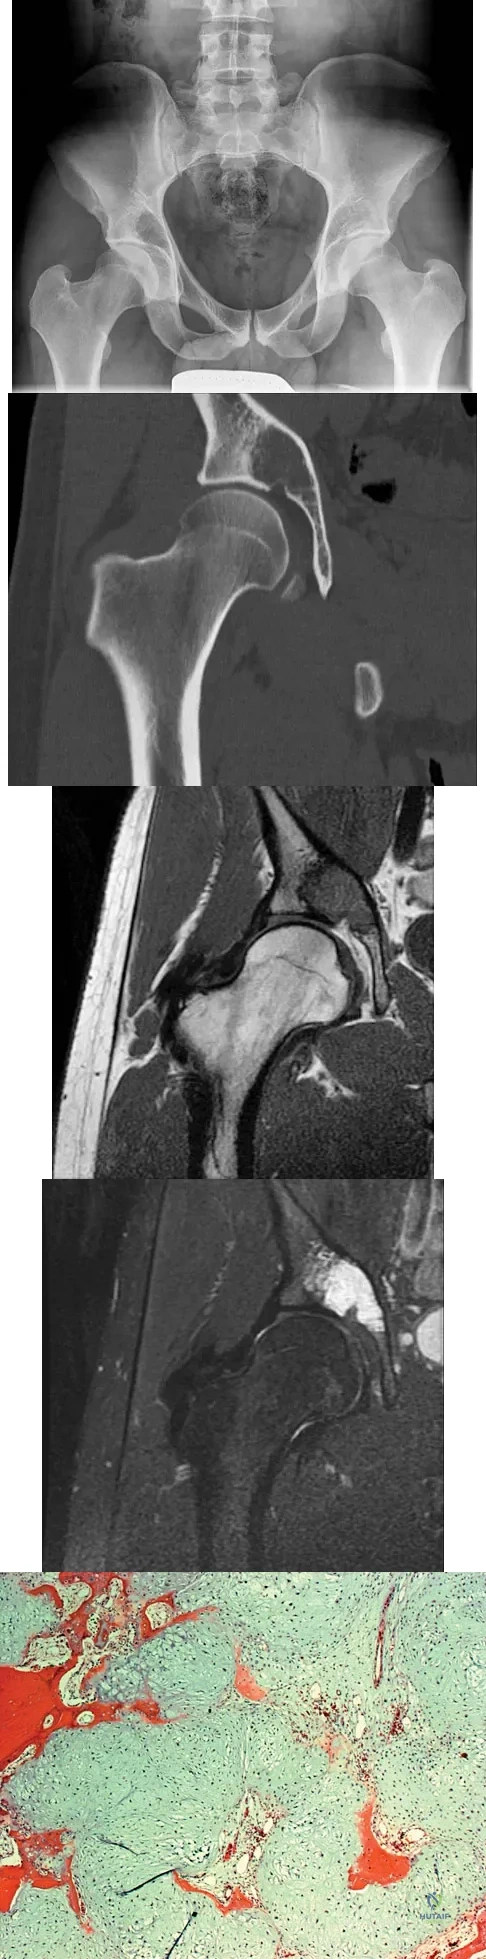

A 21-year-old man has had right groin pain for the past year. A radiograph, CT scan, MRI scans, and a biopsy specimen are shown in Figures 50a through 50e. What is the most likely diagnosis?

Explanation